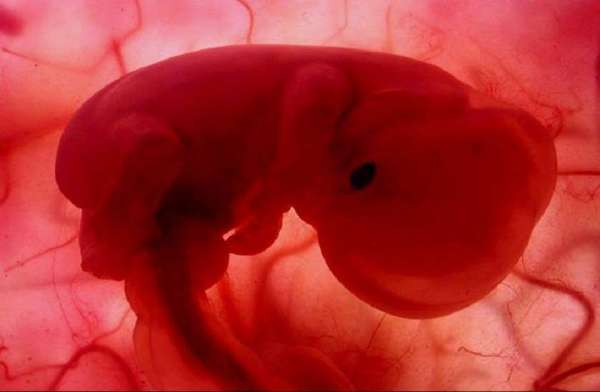

प्रेग्नेंसी के चार हफ्ते के बाद गर्भ में पल रहे बच्चे का दिल धड़कने लगता है।